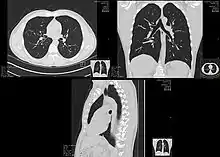

تقديم عرض تصوير مقطعي عالي الدقة للصدر. تم إزالة الجدار الصدري الأمامي والممرات الهوائية والأوعية الرئوية الأمامية لجذر الرئة رقميًا لتصور المستويات المختلفة للدورة الرئوية.